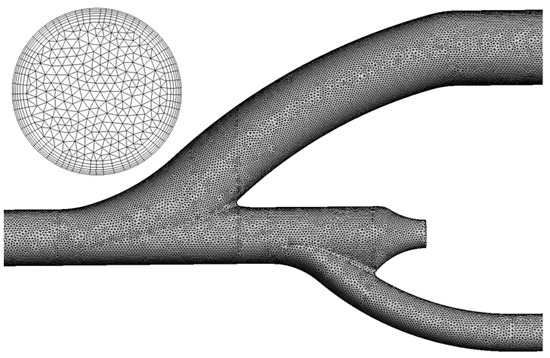

In the case of the average model, the used computational domain fully corresponded to the 3D geometry of the laboratory model of the described-above anastomosis area, with the addition of the supply tube. The calculation results shown in the present paper were obtained with a basic computational grid that included 3.2 million elements, mainly tetrahedra (Figure 5). Near the wall, the grid contained prismatic layers for a better resolution of near-wall flow. The thickness of the elements closest to the wall was about one hundredth of the diameter of the vessel. At a preliminary stage of calculations aimed at the analysis of grid dependence, two more grids, characterized by decreased and increased characteristic sizes of the elements, were also constructed, maintaining a similar spatial distribution. The coarser and the refined grids contained 500 thousand and 11 million elements, respectively. Some results of the grid sensitivity analysis are presented in Section 3.3.

Figure 5. Computational grid for the average model of the anastomosis area.